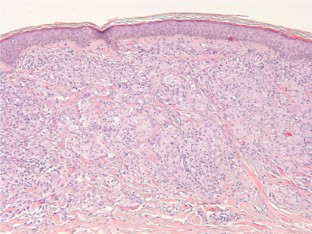

Abb. 1

Lokalisierte allergische Typ-IV-Reaktionen auf Tätowierfarbstoffe sind keine Seltenheit. Am häufigsten finden sich Reaktionen gegenüber p-Phenylendiamin, dass als schwarzer Farbstoff in temporären Henna-Tattoos verwendet wird. Generalisierte Typ-IV-Reaktionen auf Tätowierfarbstoffe sind dagegen sehr selten. Disseminiert-granulomatöse Verläufe wurden in der Literatur bisher nicht beschrieben. Wir stellen eine 54-jährige Patientin mit einem solchen Reaktionsmuster nach Tätowierung bei zuvor unbekannter Sensibilisierung gegenüber Kaliumdichromat vor.

Localized type-IV allergies to tattoo dyes are quite common. p-Phenylendiamine, which is used as a black pigment in temporary henna tattoos, is a particularly potent allergen. Generalized type IV reactions are very rare, however. Disseminated granulomatous reactions on tattoo dyes have so far not been reported in the literature. We describe the case of a 54-year-old female patient who had such a reaction pattern after a tattoo owing to a previously unknown sensitization to potassium dichromate.